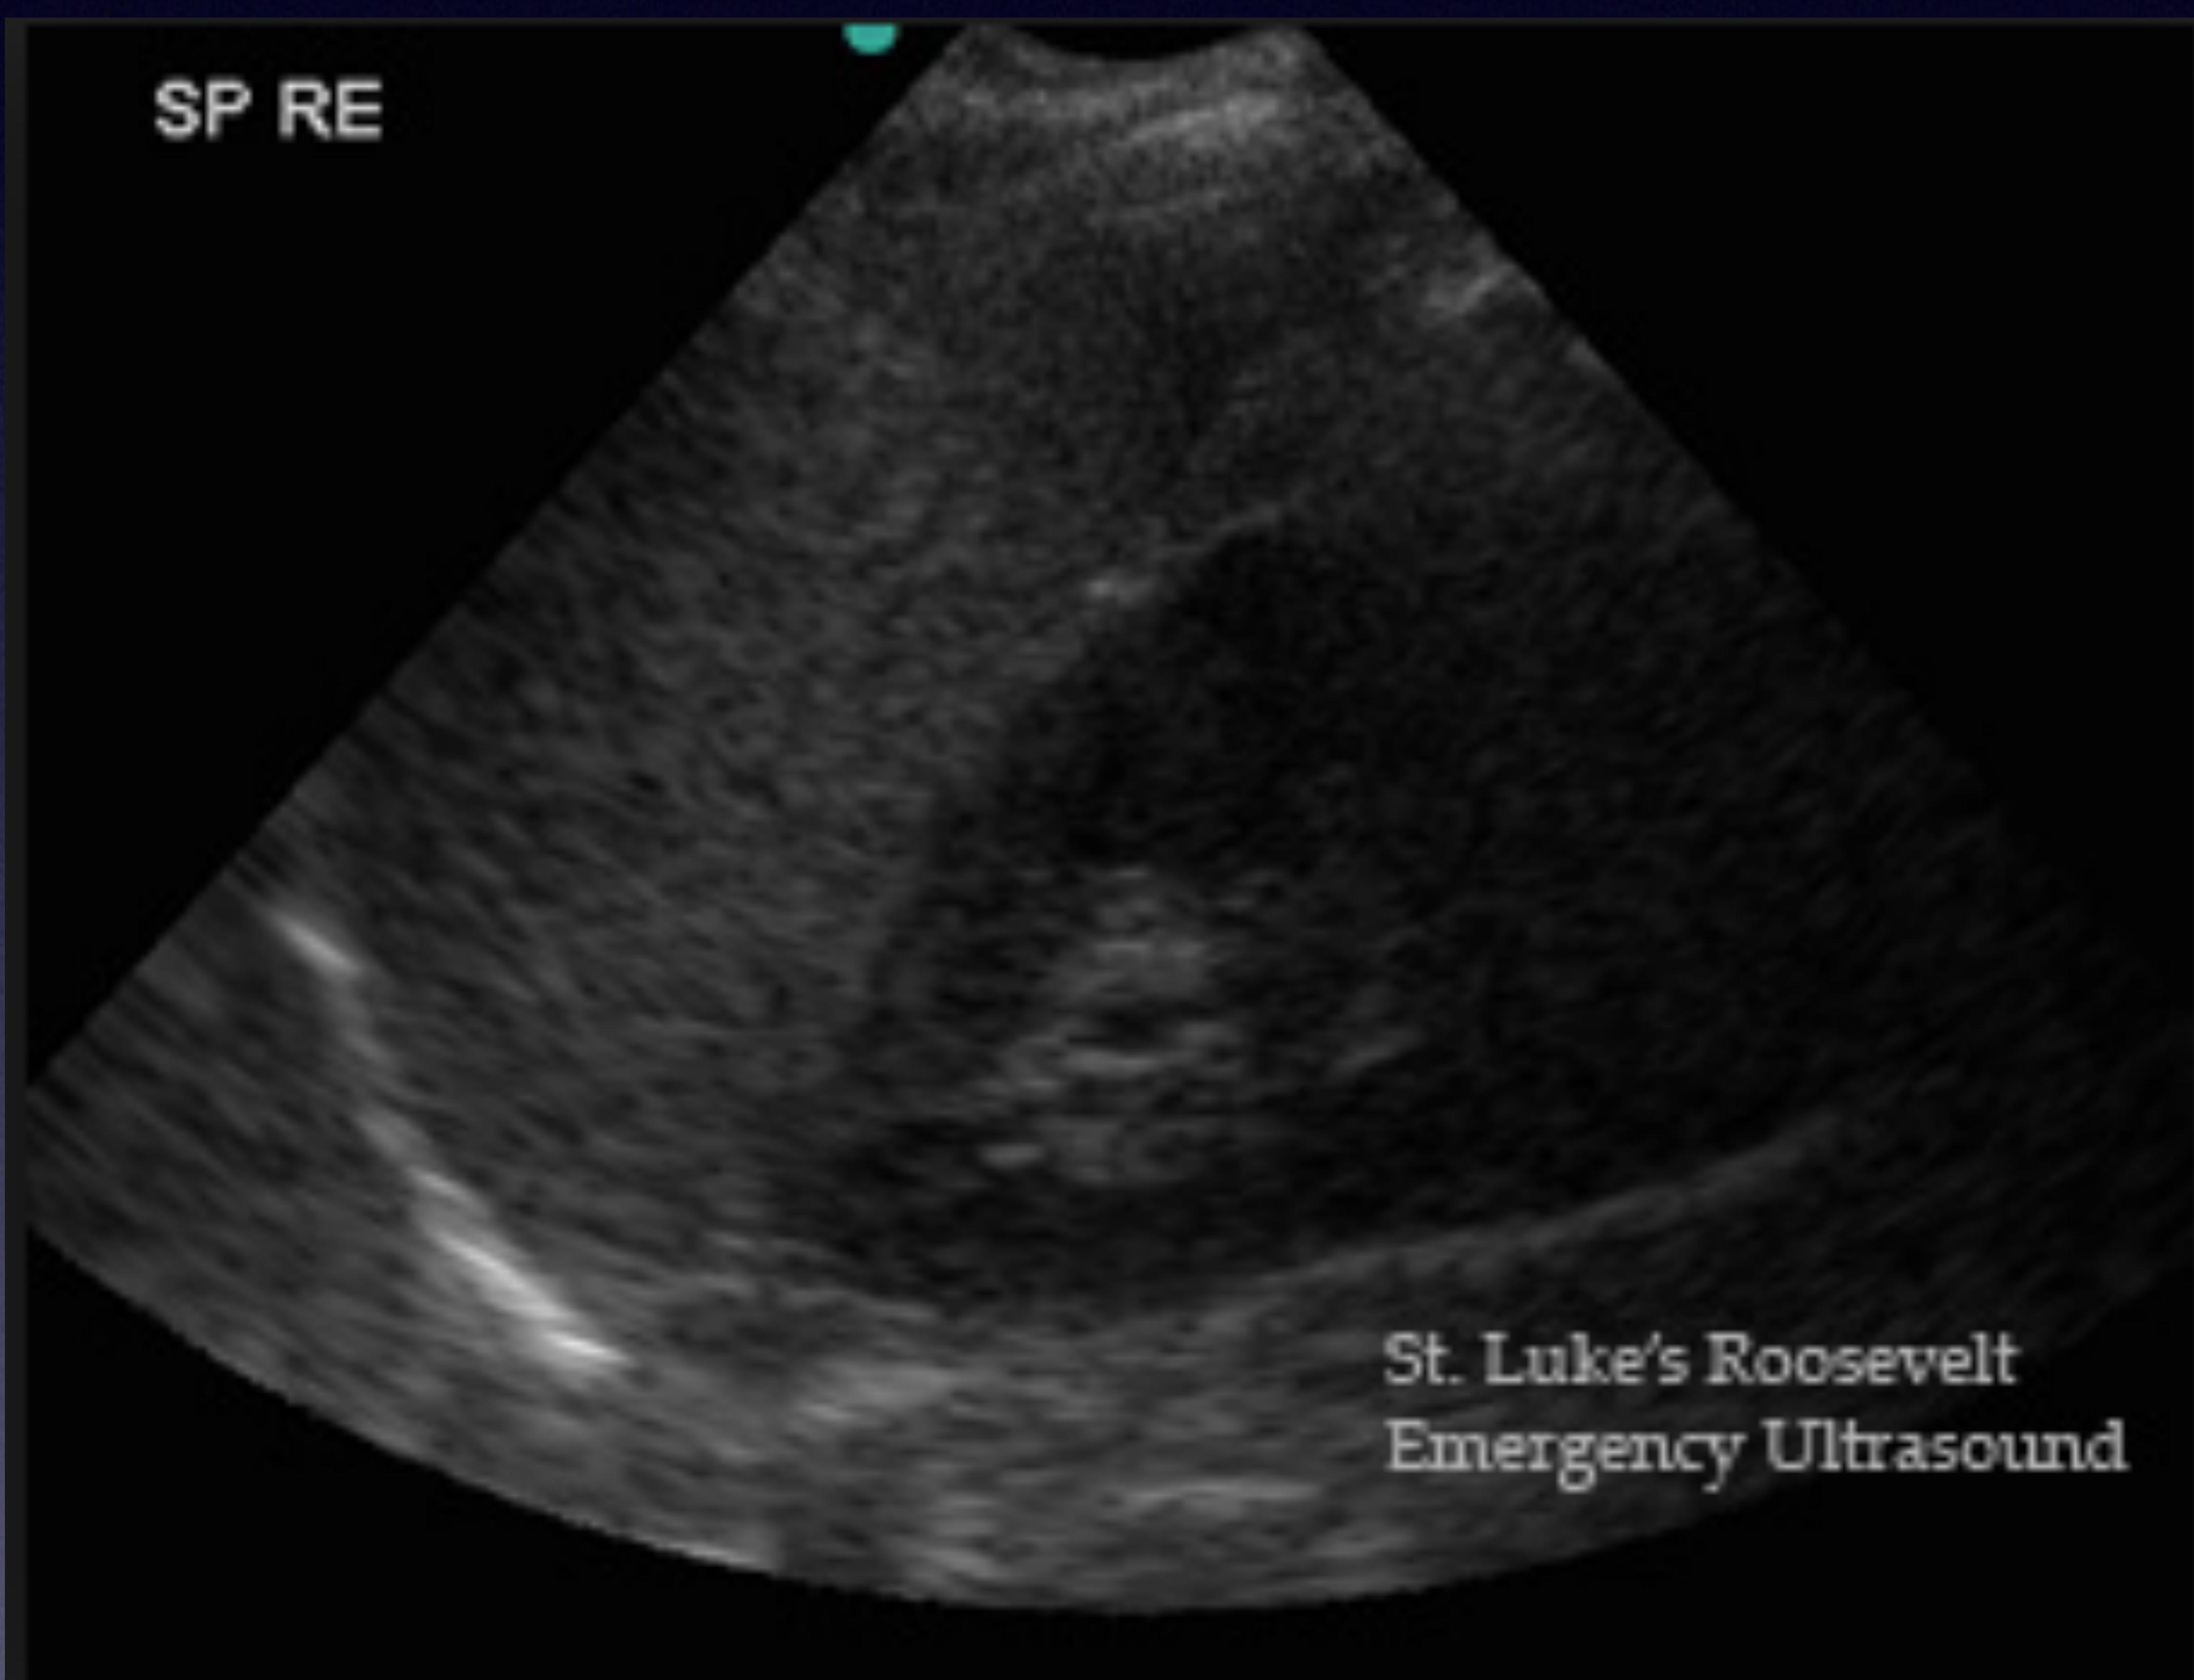

LUQ Scan (Splenorenal)

Spleen and Kidney interface.

Splenorenal view.

Spleen, Kidney, and Blood.